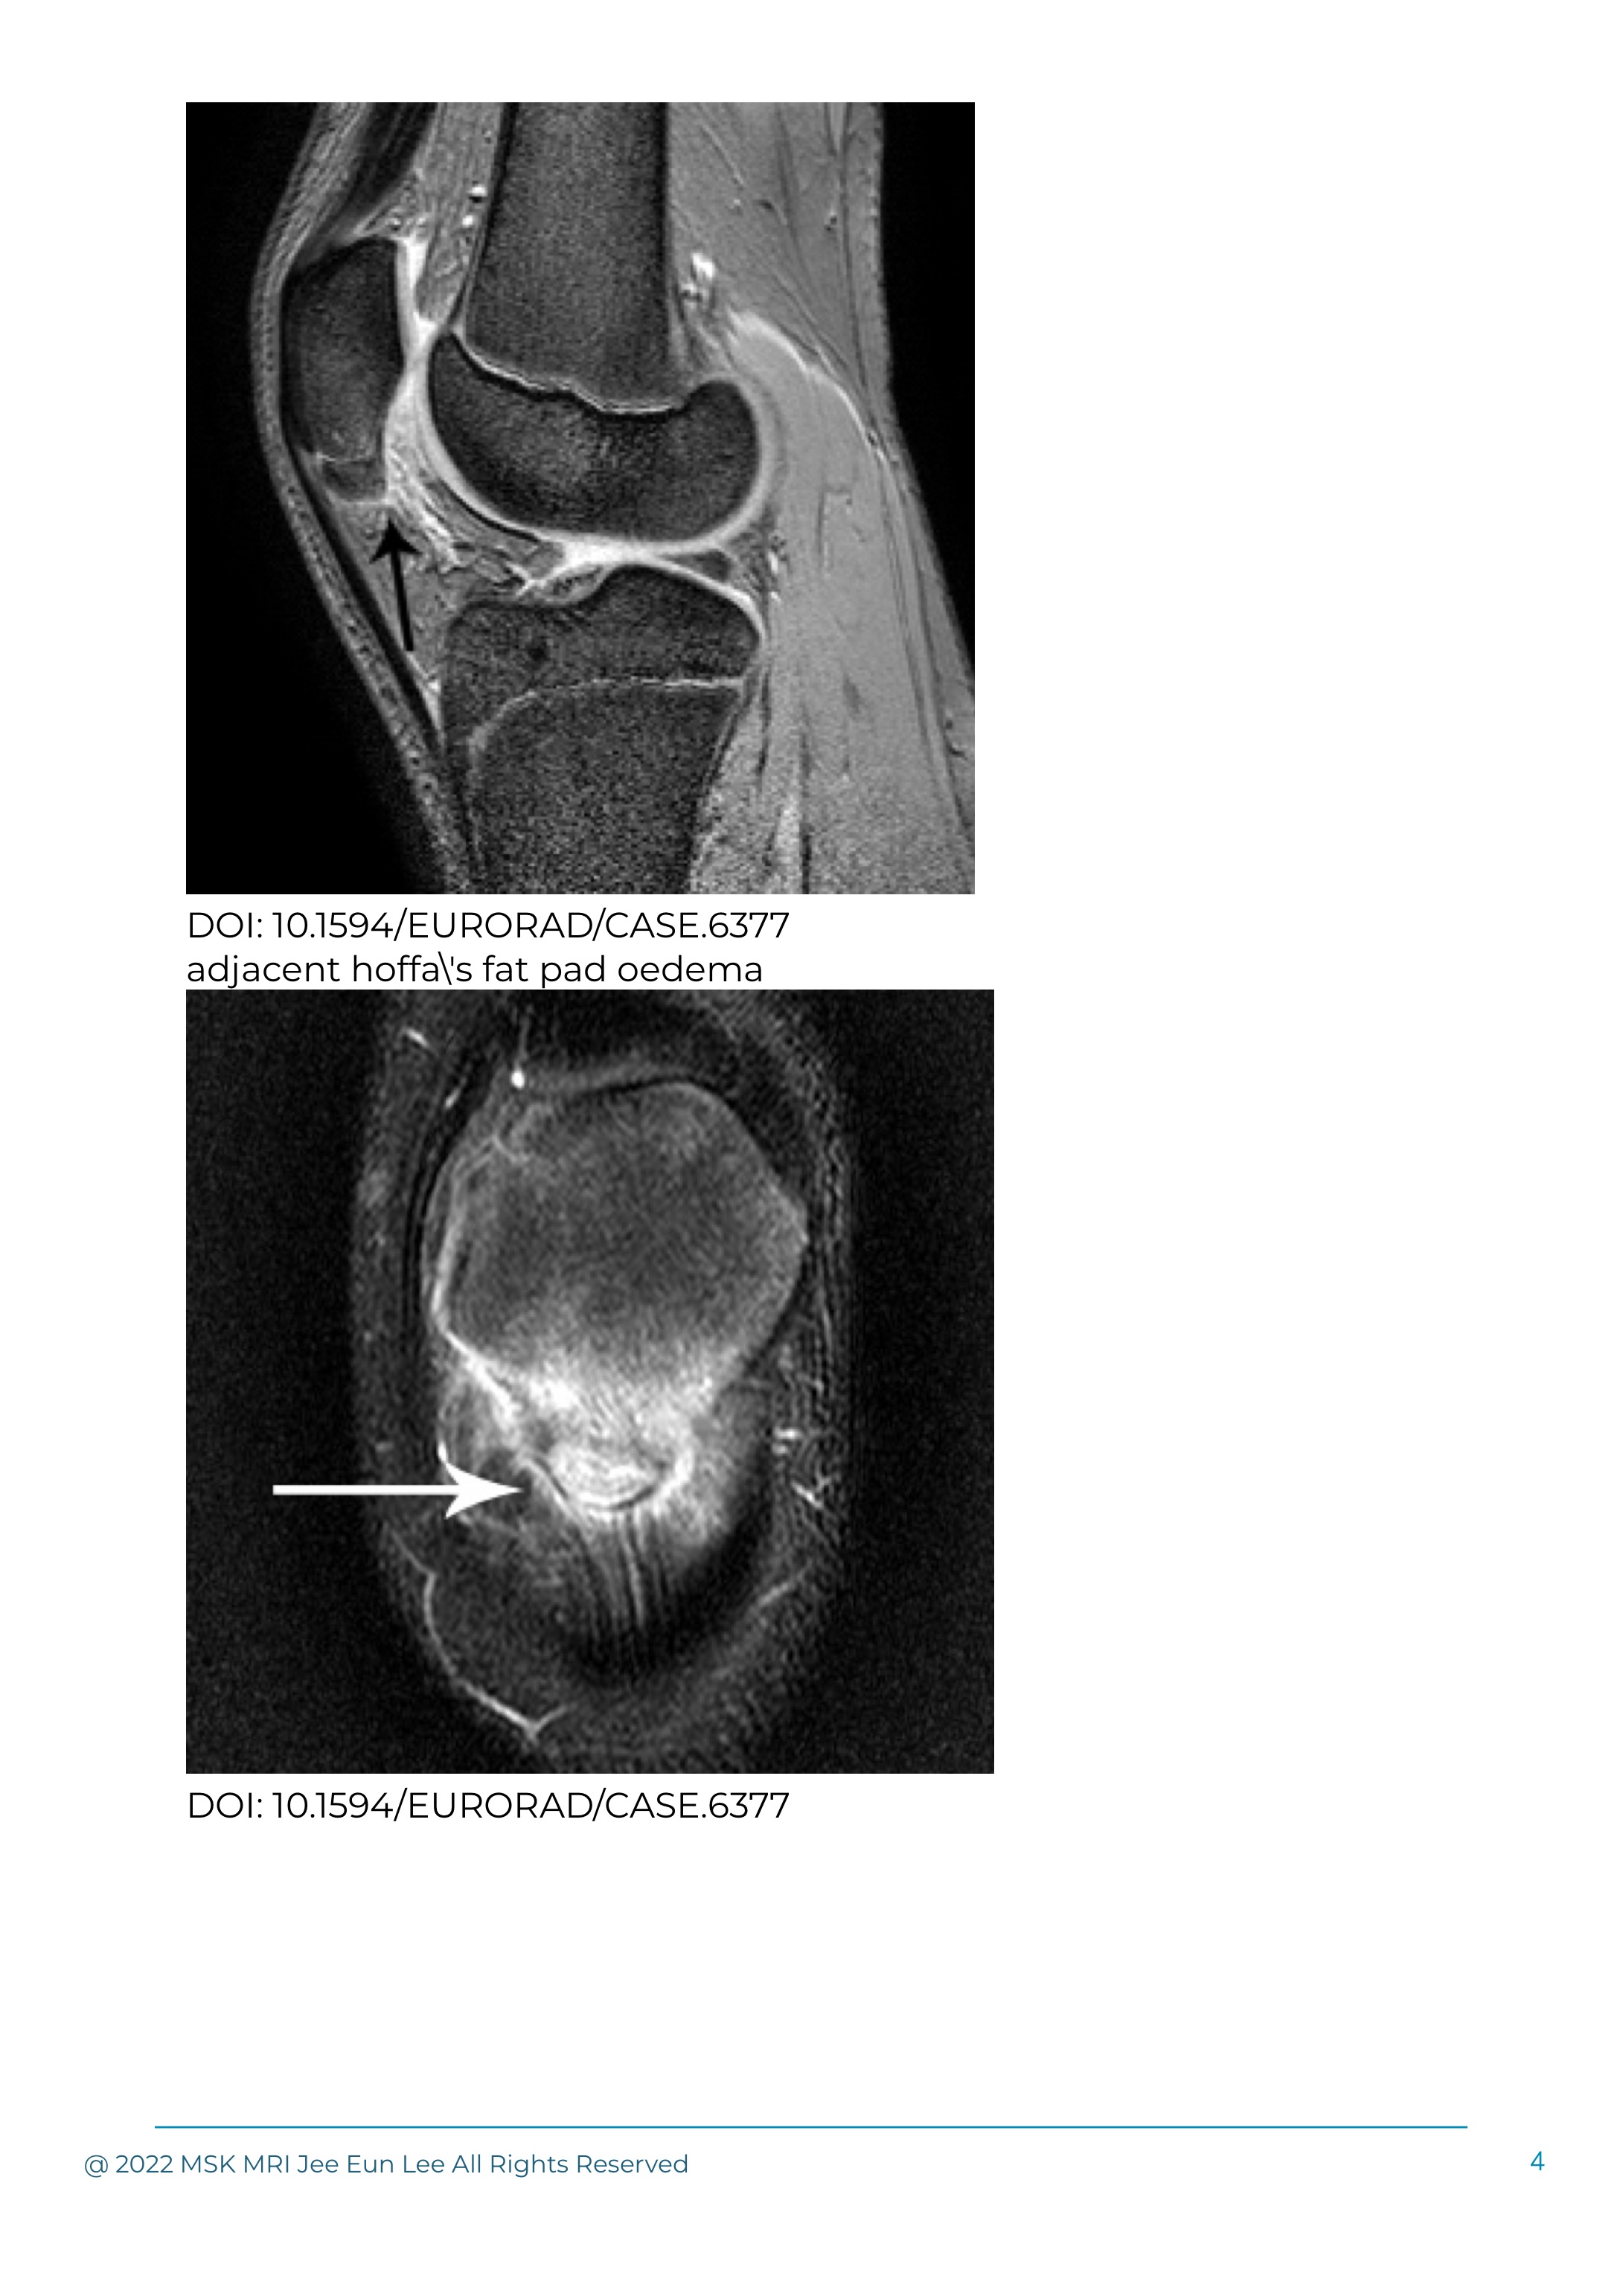

In the child, overuse injury of the proximal patellar tendon (Sinding-Larsen–Johansson syndrome) is a rare self-limiting condition.

SLJ is an enchondral ossification disorder of the inferior pole of the patella, and is part of the osteochondrosis spectrum of diseases.

It is a type of osteochondrosis at the proximal attachment of patellar ligament.

A traction tendonitis, Sinding-Larsen-Johansson syndrome results in calcification or ossification of the patellar tendon and can often be demonstrated at plain radiography.

The chronic traction at the inferior pole of the patella results in the formation of heterotopic ossification, giving a typical imaging appearance.